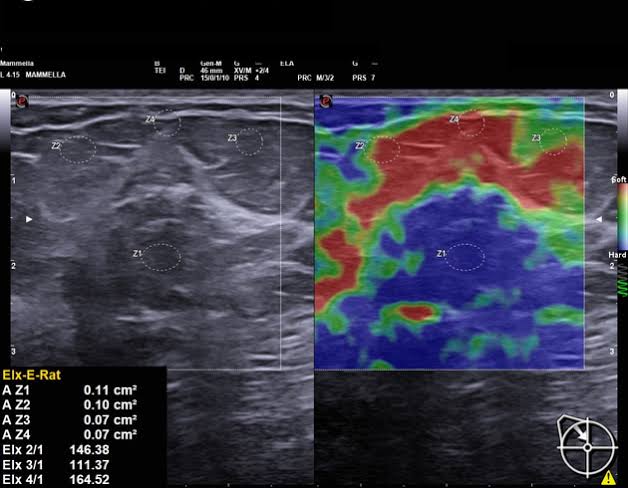

At Om Imaging Centre, we specialize in Sonography, Color Doppler, and X-ray services. Our goal is to deliver accurate and timely results, helping you and your healthcare provider make informed decisions. We strive to be the leading diagnostic imaging center in the region by offering exceptional care, advanced technology, and personalized attention.